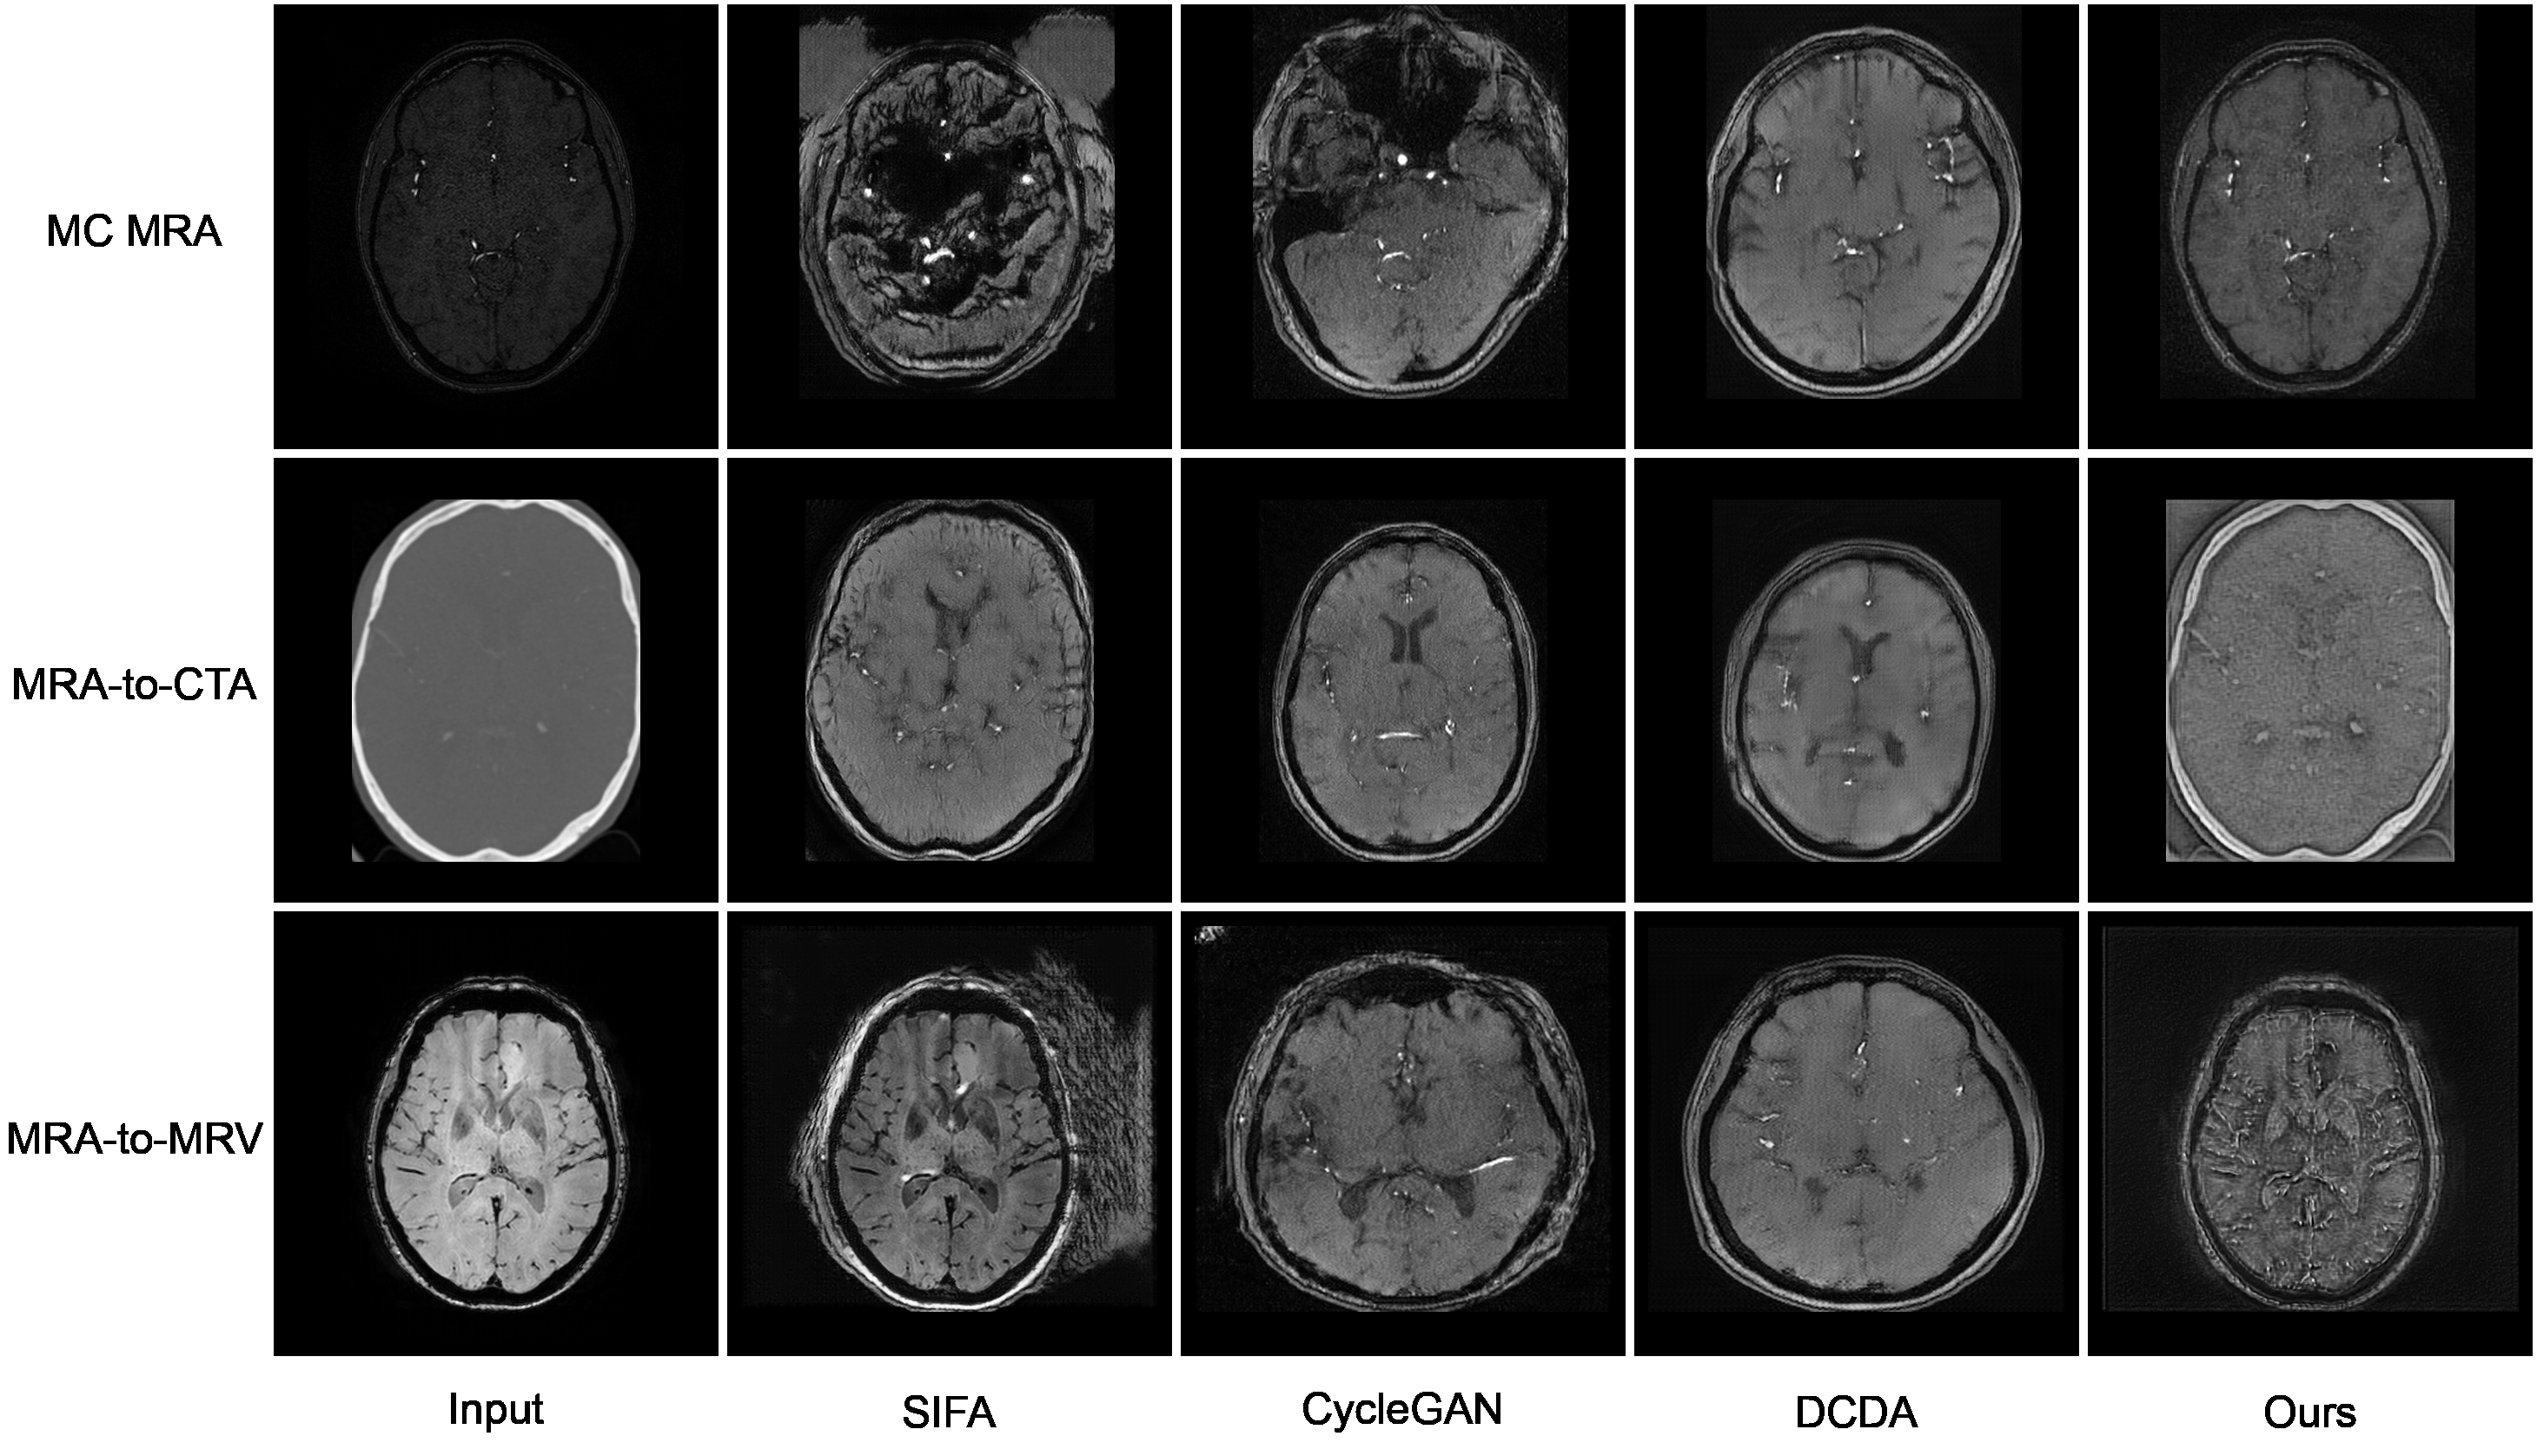

For the sake of fairness, we evaluate both cross-modality vessel and brain segmentation since most of the methods (e.g., SIFA, SynthSeg, AADG, and UniverSeg) have been developed for segmenting large objects, such as the brain. To ensure consistent comparison, all methods were retrained for brain and vessel segmentation with two exceptions: UniverSeg was used as originally designed for zero-shot segmentation on unseen medical tasks without retraining, and SynthSeg utilized its original pre-trained model for brain tissue segmentation only, as it was specifically designed for this task. Notably, while the pre-trained SynthSeg model performs well with magnetic resonance images (both MRA and MRV), it fails to segment brain tissue in CTA images due to the fundamental differences in image contrast mechanisms. Table 3 summarizes the obtained results, and Figure 5 displays a visual comparison of the results across MC MRA, MRA-to-CTA, and MRA-to-MRV.

Refer to caption

Figure 5: Comparison of the segmentation results for brain and vessels in the target MRA, CTA, and SWI images using different methods. Red indicates brain masks, while green represents vessels. The rows display slices at varying levels: top, middle, and bottom.

Figure 7: Target-to-source translations produced by the different image-level alignment methods.

Adopting the path length regularization (Karras et al., 2020) has an important role in the domain adaptation process as it allows the disentangling of the latent space 𝒲\mathcal{W}, enabling inter-domain translations that can handle independently volume-related image properties, such as overall spatial information and appearance, and vessel-related properties, such as their intensities, textures, shapes, locations, and densities. This allows preserving the target content while mimicking the appearance of a source image as it is better recognized by the segmentation branch. Keeping vessel position and shape unchanged, despite these being domain-specific features, is a key property to guarantee correct segmentation. By relying on the aforementioned capabilities, we have gathered evidence of the ability to separate the vessel-related features by visually inspecting the target-to-source translations generated by our model compared to other image-level alignment methods.

In Figure 7, we display three cases of translation: one from MC MRA (first row), another from MRA-to-CTA (second row), and a third from MRA-to-MRV (third row). These examples highlight how the different models act on the vessel-related properties. In particular, we identified three problematic behaviors that compromise the accuracy of the final segmentation results. These behaviors involve the translation of label-altering features due to their domain-specific nature. Firstly, vessels undergo displacement, resulting in changes to their position and size. This occurs while resizing the whole brain to align with the pixel spacing of the source domain. Specifically, CycleGAN and DCDA tend to translate all domain-specific features without distinction, including, in fact, the pixel spacing, and thus leading to spatial misalignment between the source and target domains. We believe this problem arises because the segmentation loss does not influence the prior translation enough, which is exactly the case in CycleGAN, where translation and segmentation are completely separate. Secondly, vessels are observed merging with the background and vanishing. This is noticeable as the number of bright vessels in the translations is never greater than the vessels in the target domain. The phenomenon is particularly evident in SWI images, where veins are generally more abundant than arteries in TOFs. The third issue arises in SIFA, which initially appears to better preserve the positions and shapes of the brain and vessels during translation, despite generating some shadow artifacts around the skull in MC MRA and MRA-to-MRV translations. However, most veins from SWIs are left untransformed and do not resemble arteries after translation. Only a few veins, likely those aligning well with the typical artery arrangement, transform into bright vessels. We attribute this behavior to the network’s inability to link arteries and veins during translation without some form of guidance.

These findings align with what was observed for Figure 5, where problematic vessels are either omitted from the final segmentation or displaced. Also, this reinforces the importance of enforcing label-preserving translations in our problem. Notably, our model uniquely transforms dark vessels from the input (SWI) into bright vessels without relocating them or reducing their number to replicate the typical arrangement of arteries in TOF MRA images. This ability to selectively translate only some domain-specific features, particularly those unrelated to vessel size and position, enables our approach to adapt veins and arteries and retrieve accurate segmentations. Lastly, we emphasize that achieving a hyper-realistic translation of target volumes is not the central focus of our model. We acknowledge that our translations may not appear entirely source-like but rather appear as hybrid representations. Indeed, the ability of the network to translate input images aims exclusively to serve the segmentation process, which is the primary objective of the proposed method.